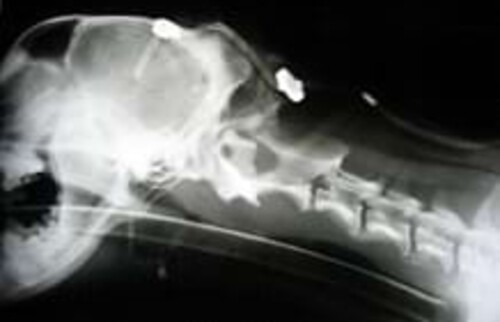

Intraoperative Durchleuchtung bei einer Behandlung.

Dafür stehen uns neben der intraoperativen Durchleuchtung 7 Verschiedene Implantatsysteme zur Verfügung, so dass wir uns immer optimal auf die Bedürfnisse des einzelnen Patienten einstellen können.